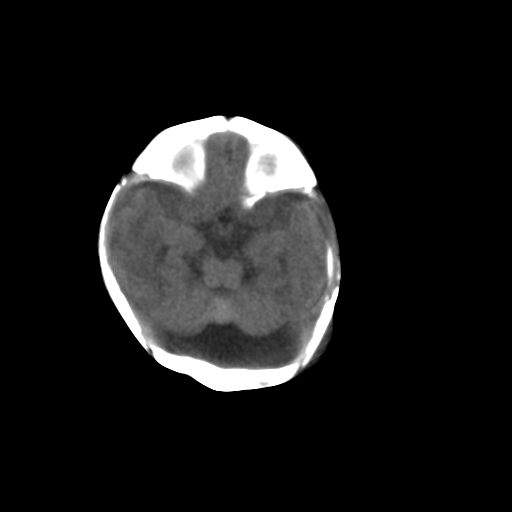

标题: PED1017:女,3天,足月顺产,出生后精神反应弱2小时。

女,3天,足月顺产,出生后精神反应弱2小时。

应该是大枕大池

依据:

1、低密度影由中线向两侧小脑表面延伸达岩锥

2、无明显占位效应

鉴别:

1、枕大池蛛网膜囊肿,常引起邻近颅骨的吸收和膨隆,枕大池蛛网膜囊肿可使四脑室前移位,伴病变以上脑室扩大。

2、dandy-walker综合征以脑积水和颅高压征常见,ct将其分为两型:

1.典型:第四脑室极度扩张或后颅凹巨大囊肿与第四脑室呈宽口相通,小脑蚓部缺如,合并脑积水。

2.变异型:第四脑室上部相对正常,可见袋状憩室从下髓帆发出,其大小、形态不一,小脑谿加宽,下蚓部发育不全、上蚓部相对正常,一般无脑积水

本例无巨大囊肿与第四脑室相通,小脑蚓部无缺如或发育不全,故不考虑

考虑 蛛网膜囊肿,建议做强化,鉴别是大枕大池其内可见造影剂、如是蛛网膜囊肿其内可不见造影剂、